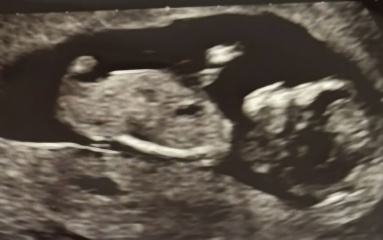

Curious about the nub theory, any guesses on what the gender could be?

Boy or Girl?